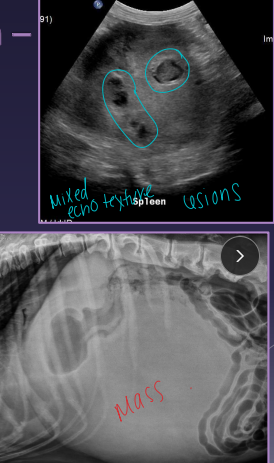

Splenic Neoplasia

Et: VERY common!

Non-neoplastic: hematoma, lipoma, myelolipoma

Benign: hemangioma, fibroma

Malignant: hemangiosarcoma HSA (#1), fibrosarcoma, liposarcoma, MCT

Sig: Lg-breed dogs

Cs: shock, mass, enlarged abdomen, fluid wave, lethargy, pain, vomiting, PCV on free fluid - determine blood, VPCs

Dt: Abd rads (mass effect, effusion, metastasis), US (mixed echotexture, cavitated lesions, enlarged spleen), biopsy

Xray chest for mets!

Tx: splenectomy